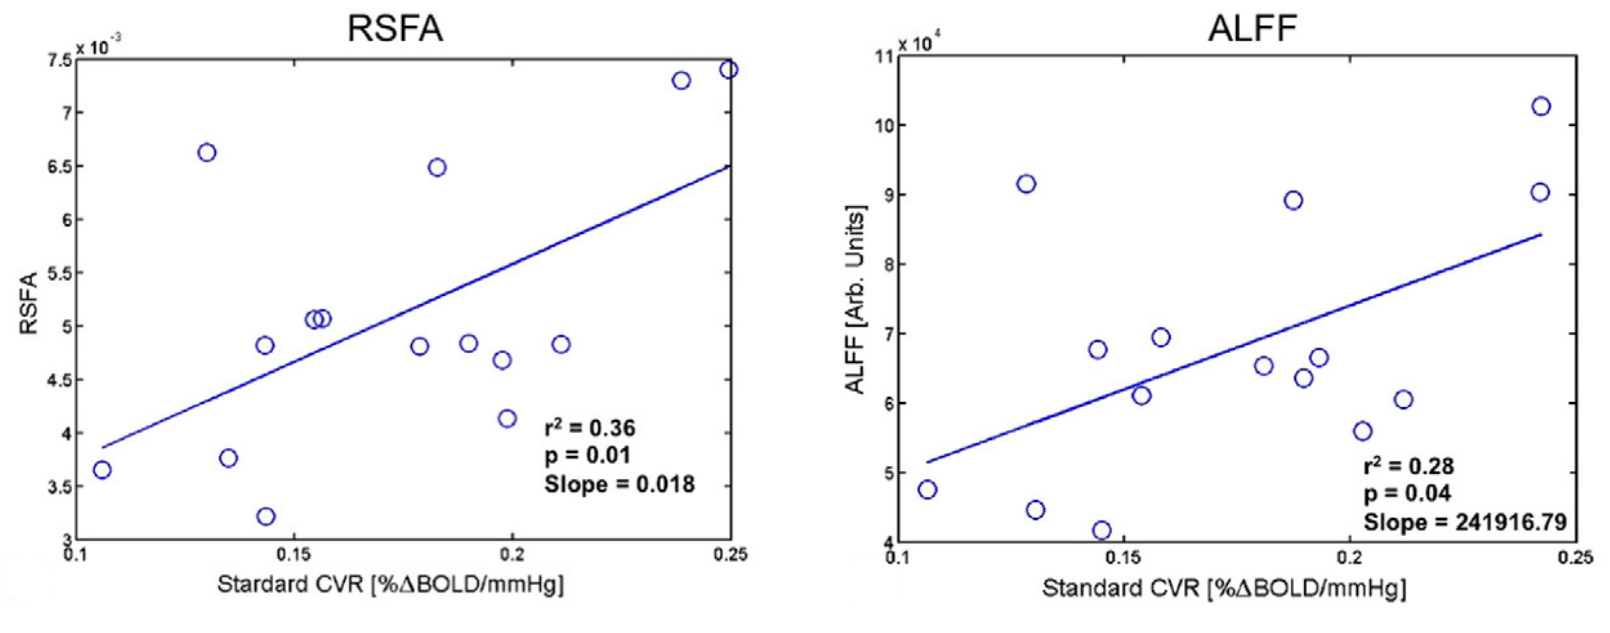

An alternative estimation of CVR (?)

2. Golestani et al. 2016 (NeuroImage)

Estimating CVR with a BH task requires compliant subjects and

dedicated equipment, making it harder to adopt in clinical practice

As a cheaper and feasible alternative, previous literature suggests to use

Resting State fluctuations measures (RSF), such as:

- Resting State Fluctuations Amplitude (RSFA)¹

- [fractional] Amplitude of Low Frequency Fluctuations ([f]ALFF)²

1. Kannurpatti et al. 2014 (PloS ONE)

An alternative estimation of CVR (?)

Results: CVR and RSF

Physiology and RSF

We used 3dLMEr¹ to set up the following LME models (R syntax):

Effect of Sex

Only sex had a significant effect on RSF

Effect on CVR

Results: CVR and RSF

Golestani et al. 2016 (NeuroImage)

- We did not observe a statistically significant effect of CVR on RS fluctuations, or of CVR and RS fluctuations on task induced activity, most probably due to the high variability between subjects

The failure of generalisation of previous observations might be related to different methods, but whether this is related to a better denoising and signal quality or to a possibly non optimal setting (e.g. compared to gas challenges) is uncertain

A different statistical perspective (i.e. Bayesian) is required to exclude any relationship between CVR and RS fluctuations, and further analyses are required to improve the agreement between CVR and RS fluctuations